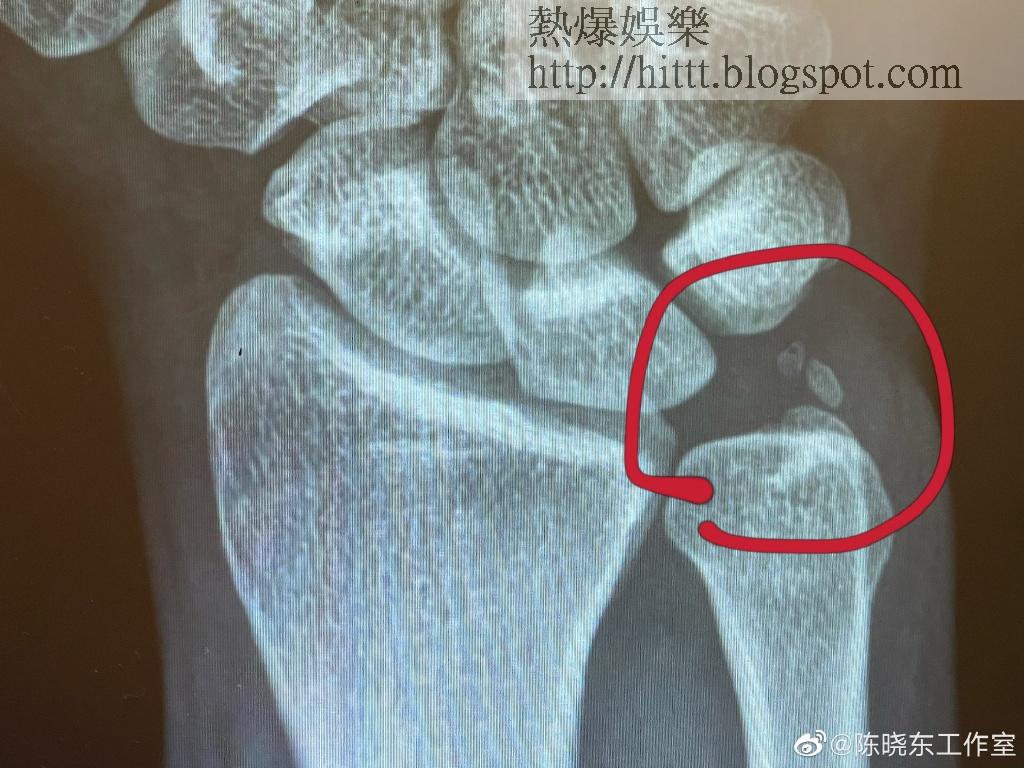

今日,陳曉東的工作室在微博貼出X光相及右手戴着護具的照片,留言表示陳曉東在一個多月前,手腕一直隱隱作痛,不過因為他以為是自己用力不當而扭傷,所以未有理會。但一個月後,陳曉東轉動手腕時,除了覺得痛外,亦不能拿重的物件,故最後便去照X光,結果發現手腕處有兩塊碎骨外,手腕的韌帶亦受傷,所以現時他遵照醫生叮囑戴上護具,一個月後再視乎情況決定下一步治療方法。雖然碎骨兼韌帶受傷,看似傷勢不輕,但陳曉東就似乎好怕開刀,他留言說:「先戴着這個護具,等它好。不願手術取。」